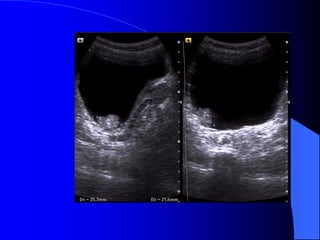

* Siãu ám: Hçnh cáöu, räùng ám, tàng ám sau, båì âãöu

khäng tháúy roî thaình nang. (Nãúu âuí caïc tiãu

chuáøn trãn, âäü chênh xaïc laì 100%.)

* CLVT: Nang coï tè troüng tháúp = dëch (10  

20UH), âäöng nháút, giåïi haûn âãöu roî, khäng tháúy

thaình, khäng ngáúm TCQ. Âäü chênh xaïc cháøn

âoaïn 100%.